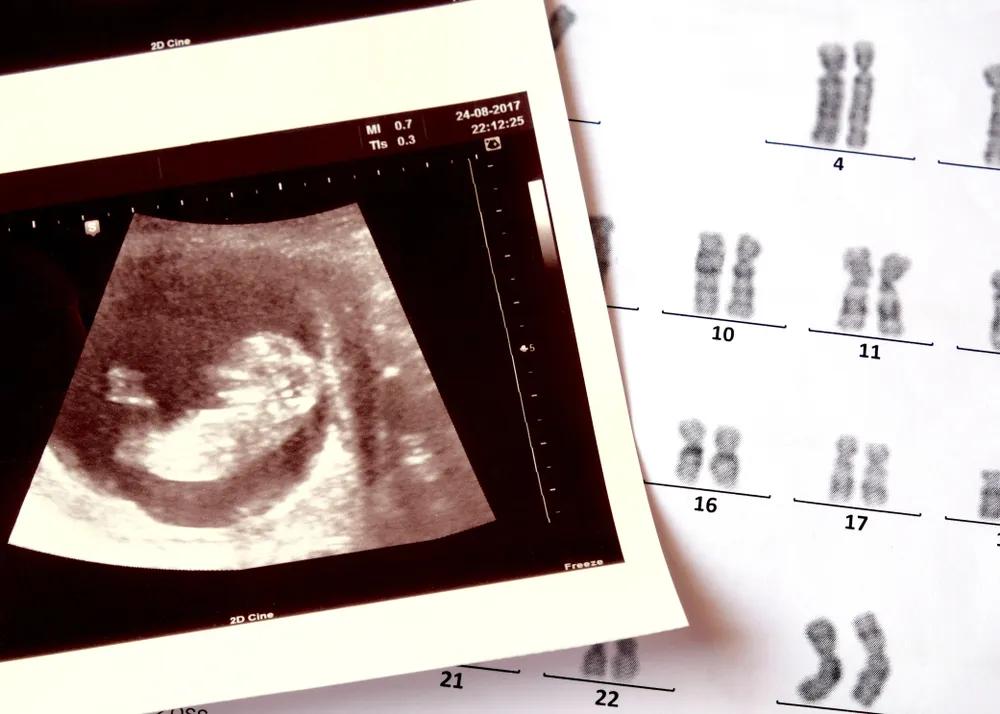

很多生育障碍的夫妇,寄希望于试管等生殖技术,来改变生活状态,但技术的不确定,让焦虑卷土重来,很多女性被身体受创与生殖焦虑反复拉扯。

曾纪琪夫妇正在尝试试管婴儿。

根据中国人口协会、国家计生委联名发布的《中国不孕不育现状调研报告》显示,中国的不孕不育发病率在 12.5%~15% 左右,患者人数超过 4000 万,占到全部育龄人口的 12.5% 。

为了尽可能排除那一点点因素,曾纪琪和黎晓都选了更明确的方案 —— 试管。

曾纪琪决定做试管之后,开始进入各种各样的试管群和求子论坛和不同的人聊天,她看到群里有不少人经历过四五次的、甚至有十几次还没有成功的,很多人是从安徽、苏北一些县和农村来到南京租房子做试管,最低费用的一代试管,一次也需要 4~5 万,很多人举债十几万仍未成功,她想给自己打个心理上的预防针。